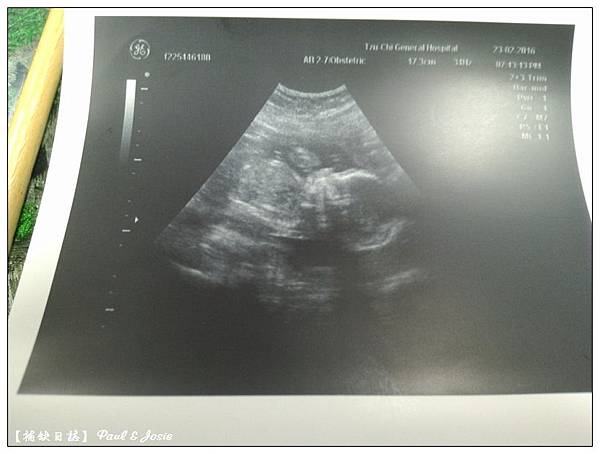

2016/04/19第六次產檢 27w+5d 女寶寶頭骨橫徑6.88cm,1040g 。

2016/05/03 第七次產檢 29w+3d 女寶寶頭骨橫徑7.3cm,1290g 。